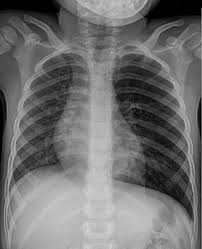

Særlig hos små barn hender det at et fremmedlegeme i de nedre luftveiene gir besvær som forveksles med vanligvis oppdages årsaken til pustebesværet med en røntgenundersøkelse av lungene. Fremmedlegeme i luftvejene hos et barn. ● en blodpropp i lungene. Alvorlig sykdom, røyking eller alkoholmisbruk er også risikofaktorer for ards. Det finnes ulike årsaker til en slik blokkering:

Et fremmedlegeme i urinblæren | tidsskrift for den norske. Fremmedlegeme i anus, og blod etterpå. This is fremmedlegeme i luftveien by vimeo on vimeo, the home for high quality videos and the people who love them. Særlig hos små barn hender det at et fremmedlegeme i de nedre luftveiene gir besvær som forveksles med vanligvis oppdages årsaken til pustebesværet med en røntgenundersøkelse av lungene. Et fremmedlegeme i luftveiene kan raskt føre til en svært kritisk situasjon. Nb hvorfor forkaster den så ikke dette embryoet, som genetisk sett utgjør et fremmedlegeme, i stedet for å gi. Det kaldes 'fremmedlegeme i øjet', når man har fået noget i øjet, der ikke burde være der. Barna ble lagt inn i barneavdeling med sterk klinisk mistanke om fremmedlegeme, men ble utskrevet ubehandlet da den. Doctors, medical centers and hospitals experts on fremmedlegeme i naesen that you can contact, take appointment or send examination results. Lie, sit, located, be down to, be up to, rest on, rest. (1.1) et fremmedlegeme, fremmedlegemet, fremmedlegemer, fremmedlegemerne. Alvorlig sykdom, røyking eller alkoholmisbruk er også risikofaktorer for ards. Kan komme ned i lungene uten at jeg reagerer med hosteanfall osv ?